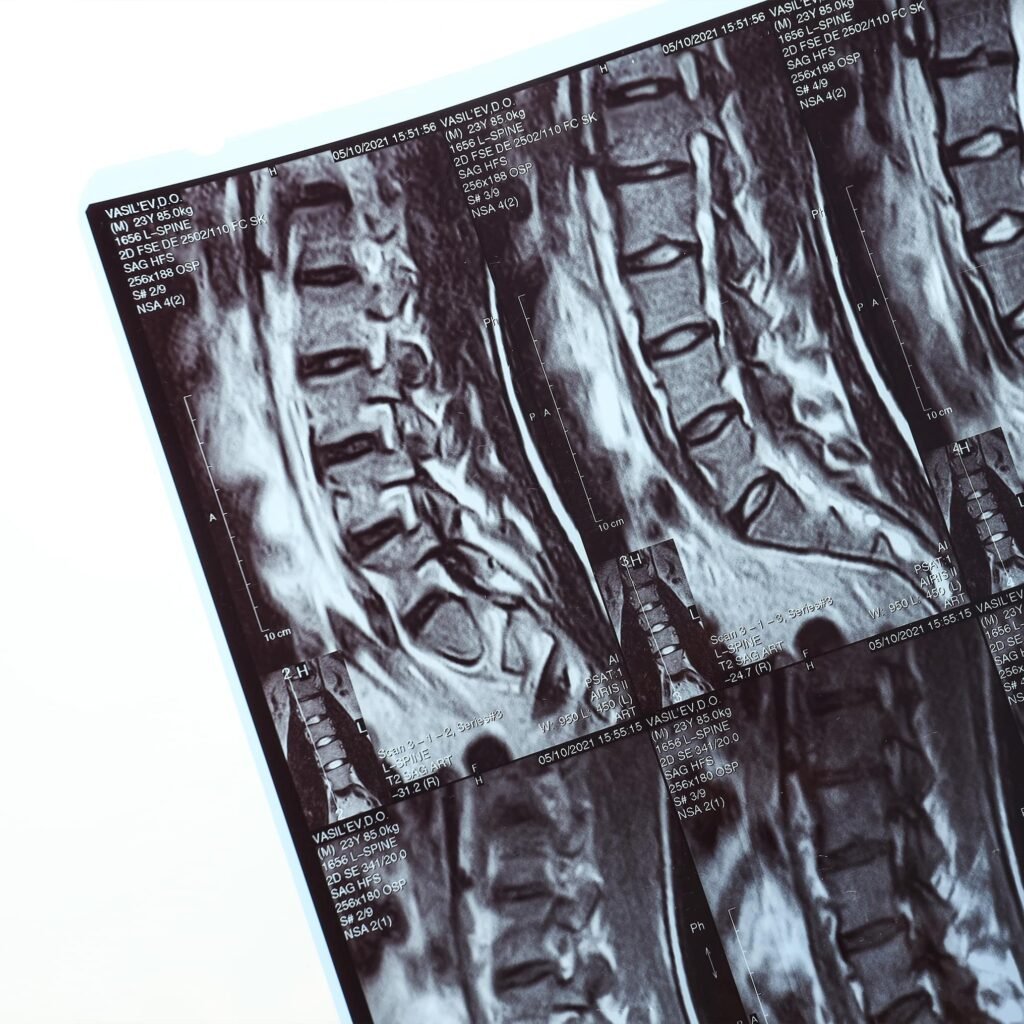

Lumbar Spinal Stenosis

Lumbar Spinal Stenosis is the narrowing of the spinal canal in the lower back, leading to nerve compression. Symptoms include back pain, leg pain, numbness, and weakness. Treatment ranges from conservative measures such as physical therapy and medications to surgical decompression when conservative care fails.